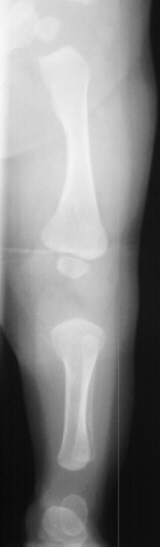

A 6 month old Amish infant female was referred for symmetric polydactyly of both hands. Prior to her presentation in our clinic she was seen and evaluated by a cardiologist for an apparent congenital heart murmur. On physical examination of the upper extremities there was a sixth digit on the ulnar border of both hands. The finger nails appeared to be dysplastic.

As the child grows a short-limbed disproportionate dwarfism will likely become more apparent

As the child grows, she may develop varus deformity of the knees. These deformities do not respond to orthotic treatment and may need osteotomies for correction.